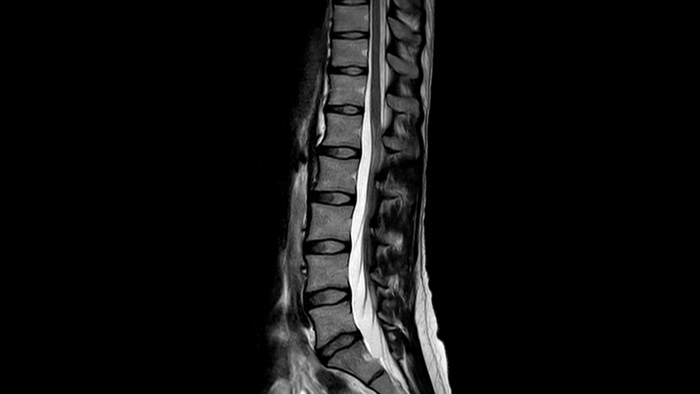

Medio de la columna

Velocidad

Realice exámenes de resonancia magnética hasta un 50% más rápidos2, para que pueda emplear su tiempo de manera inteligente.